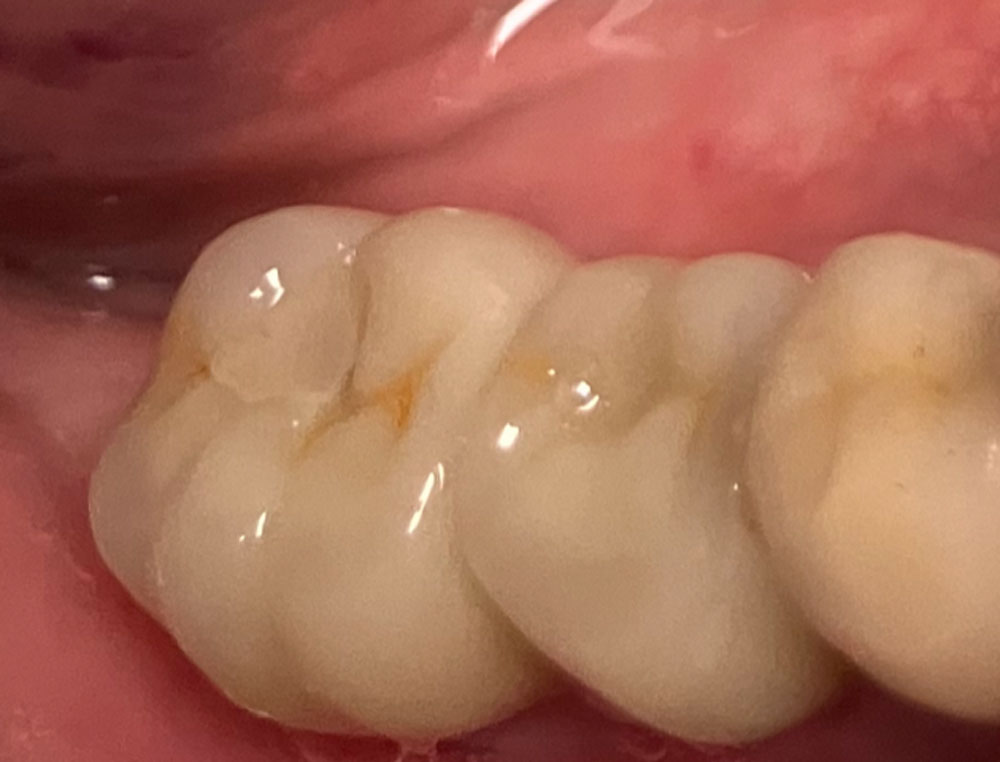

La cicatrisation est favorable et les implants s’intègrent dans un environnement osseux et gingival stable.

Les couronnes céramiques présentent une intégration esthétique satisfaisante.